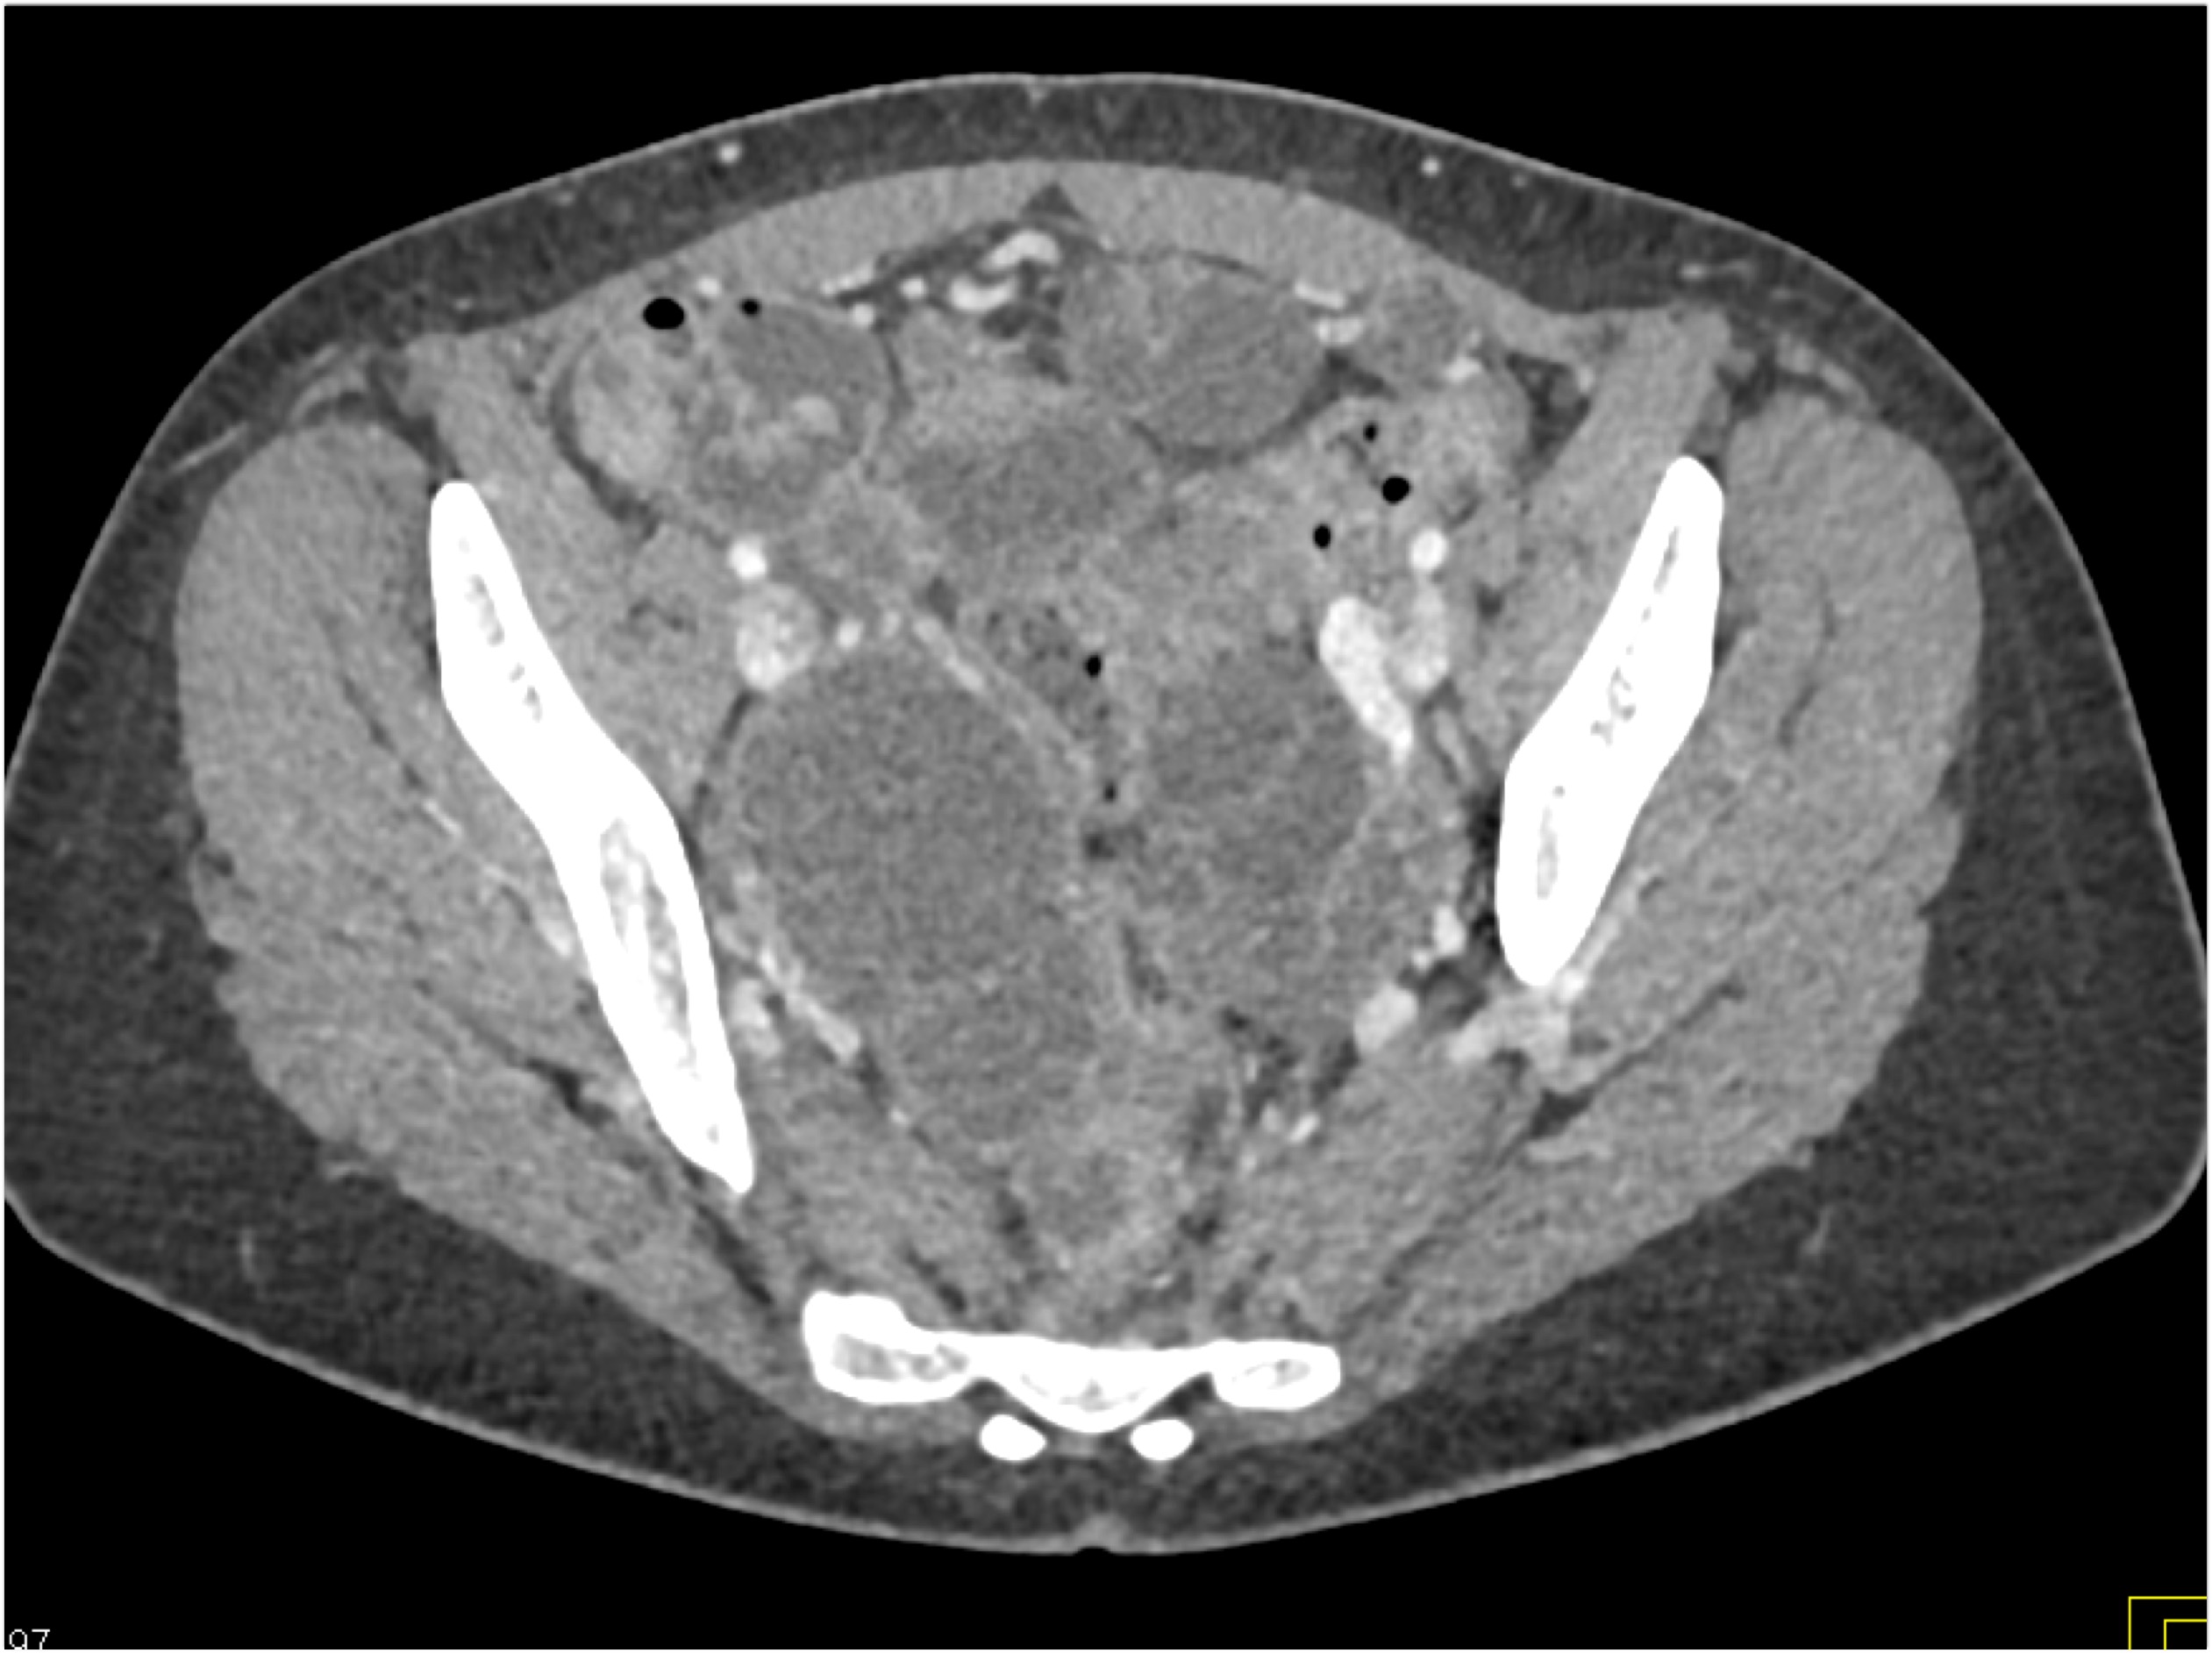

- Evaluate the CT images of each question carefully.